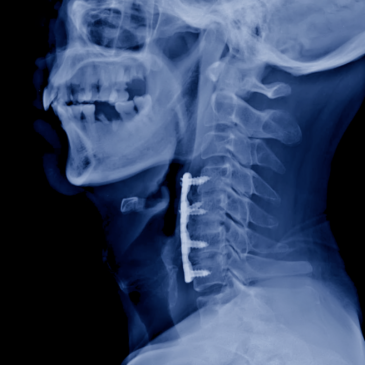

I’m sharing a story submitted through my website about an unsuccessful spine surgery, which is, sadly, all too common. This issue even has a name: “failed back surgery syndrome” (FBSS). Most of these surgeries start with operating on normally aging spines that don’t actually cause pain. The data shows this … Read More